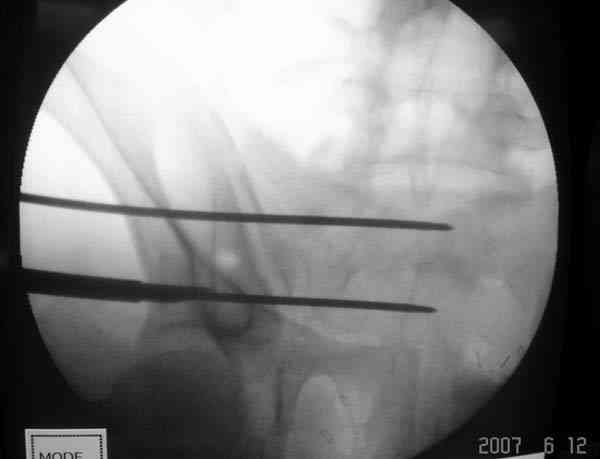

Проведение сверла под неврологическим мониторингом уменьшает риск повреждения нервов во время операции.

SI potential monitoring